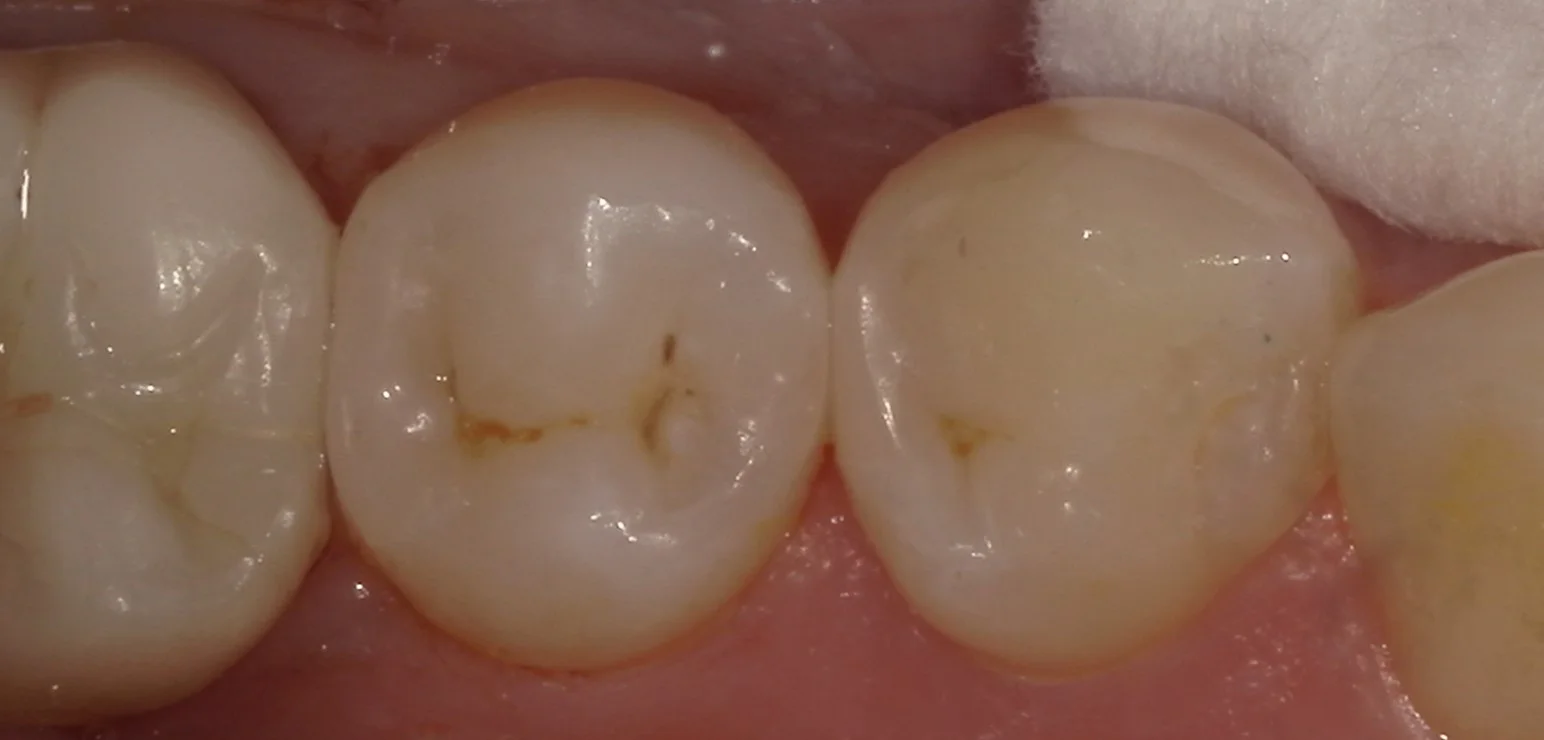

そして詰め終わったのがこちらです。

違和感なく綺麗に仕上げられたかと思います。

最近研磨の手法を切り替えたのですが、ツヤが良く出るようになって更に自然になるようになってきましたね。